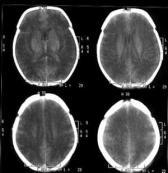

缺血缺氧性腦病癥狀

• 缺血缺氧性腦病

628健康網為您分享有關缺血缺氧性腦病的癥狀,缺血缺氧性腦病的治療方法,缺血缺氧性腦病的預防知識,缺血缺氧性腦病的癥狀...